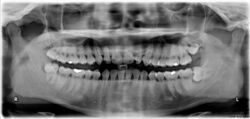

The upper left (picture right) and upper right (picture left) wisdom teeth are distoangularly impacted. The lower left wisdom tooth is horizontally impacted. The lower right wisdom tooth is vertically impacted (unidentifiable in orthopantomogram).

Dental x-ray of impacted lower left wisdom tooth with a horizontal orientation